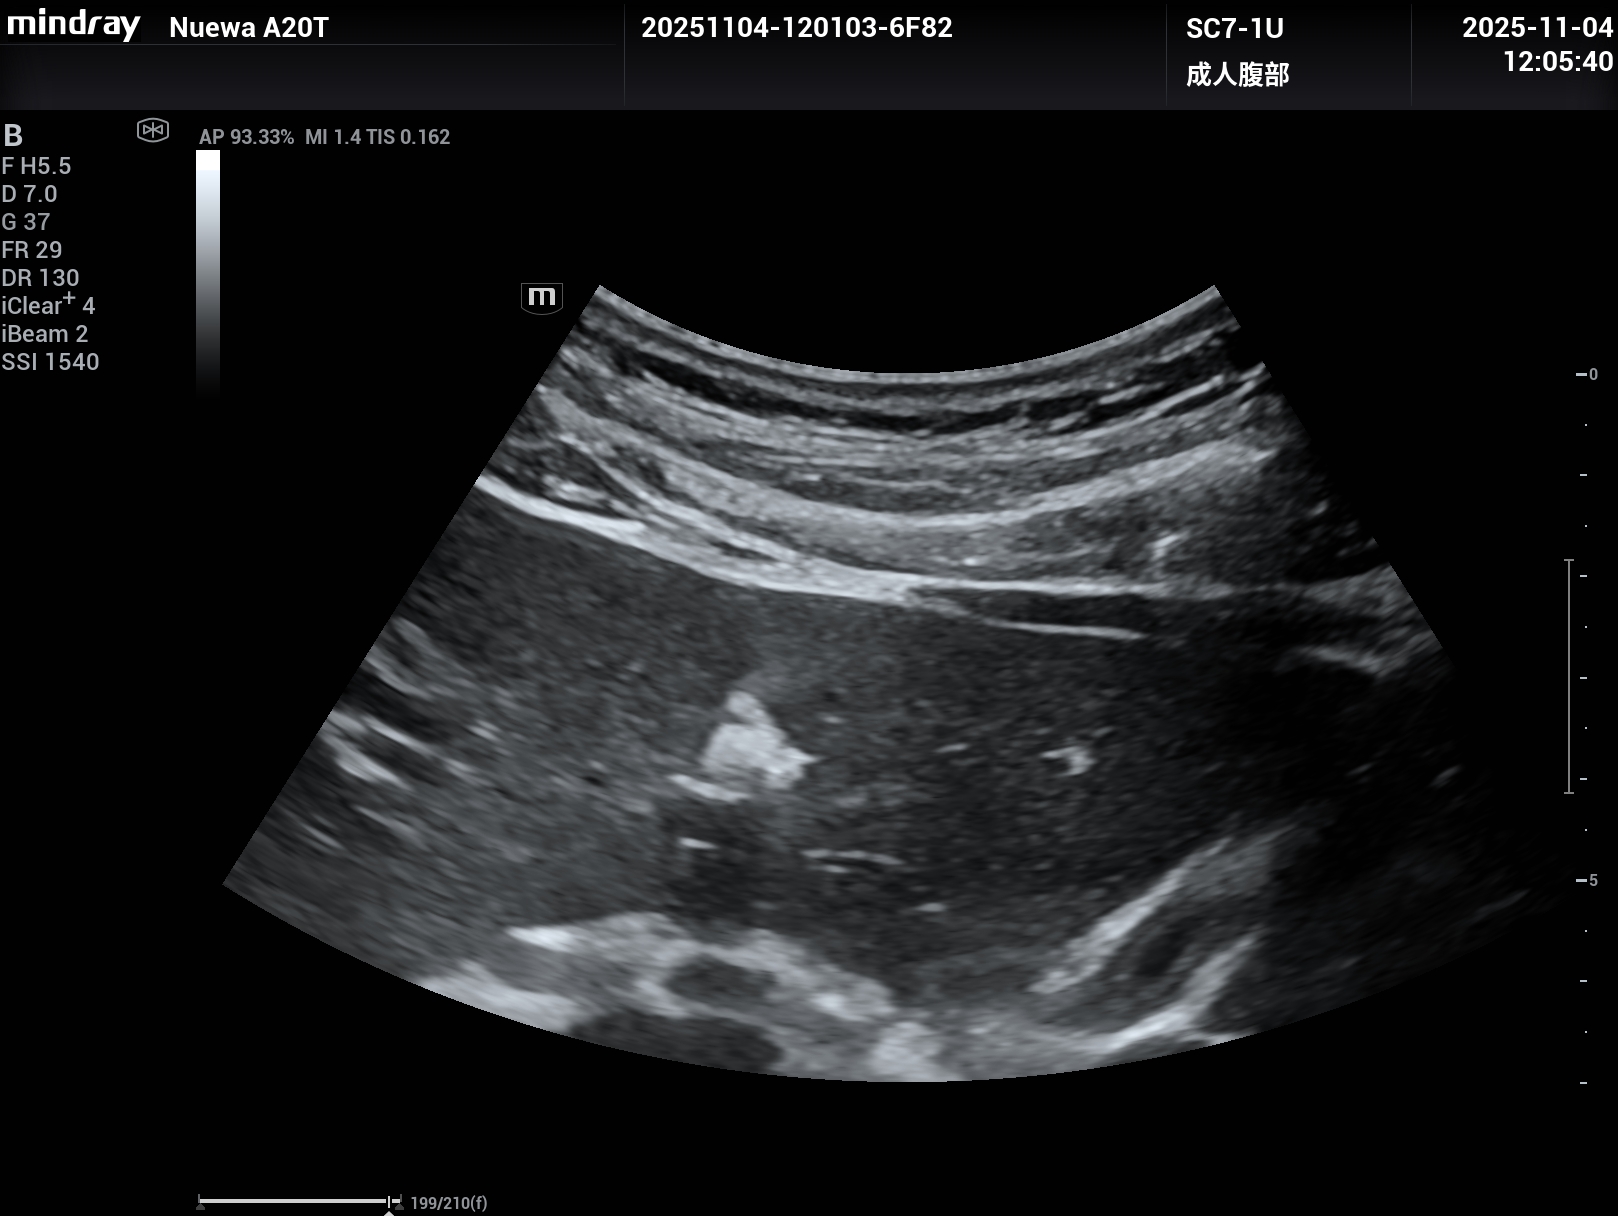

睿瞳技术,是具有独立的发射和接收电路设计的成像技术,组织回声信息更多,图像信息更丰富。

上2幅图是采用了Nuewa A20睿瞳技术的图片,下2幅是没有采用睿瞳技术的图片。